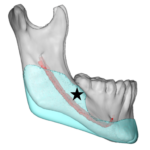

Jaw angle implants are most commonly placed through an intraoral approach without visible external scars. With bilateral posterior vestibular incisions that are up out on the cheek opposite the 2nd molar tooth, subperiosteal dissection is done to elevate the masseter muscle off of the bone. Depending upon the type of jaw angle implant being used, Read More…